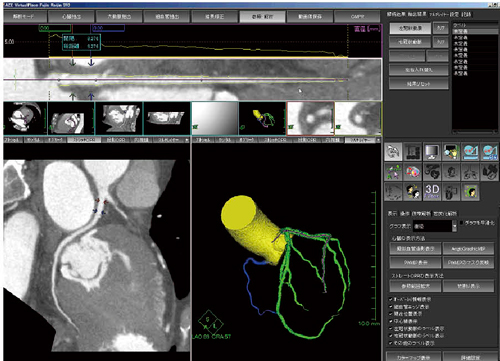

そこで,冠動脈CT即時読影における自動解析ソフト“AZE Auto Analyser”の有用性を検討した。読影法1はsliding thin slab MIP法のみ,読影法2 はsliding thin slab MIP法に加えて自動解析結果のボリューム読影を行っているが,その結果,acurracyが読影法1では88.5%,読影法2では95.2%と有意に向上した。特に,冠動脈硬化症例やステント挿入症例において,自動解析によって冠動脈の中心線がしっかりとトレースできたことで,診断能の向上につながったと考えられる。また,AZE Auto Analyserでは,狭窄長の計測や狭窄率の測定なども自動で行うことができる(図2)。

図2 AZE Auto Analyzerによる自動解析